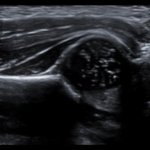

- Ecografia de caderas pediatrico